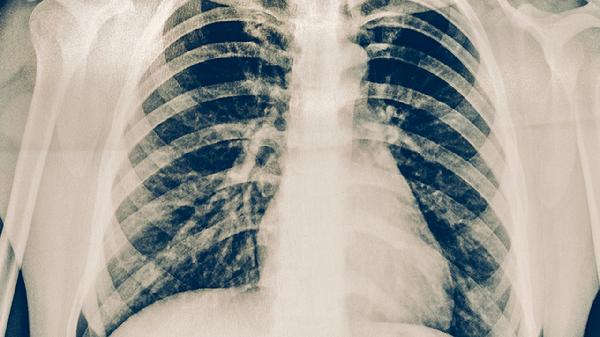

宝宝咳嗽导致肺损伤

宝宝咳嗽导致肺损伤,可能是由于感染、异物吸入、过敏反应、手术因素等导致。若宝宝咳嗽导致肺损伤后,出现呼吸困难等不适症状,建议及时就诊,并在医生指导下及时进行相应治疗。 1、感染:若宝宝咳嗽的症状较重